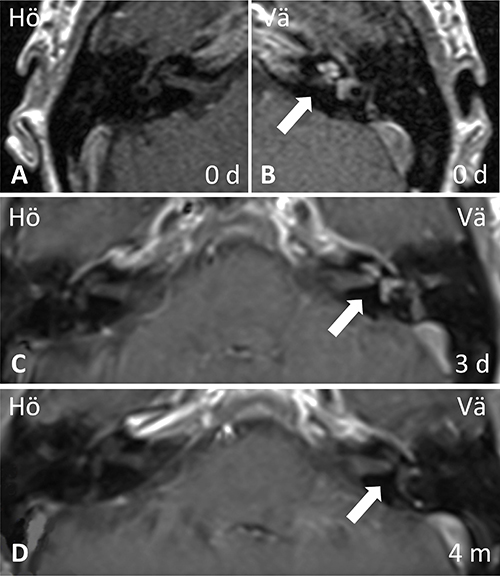

Patienten lades in för kortisonbehandling i hög dos, men något dygn senare tillkom plötslig irritation i höger öga och dimsyn. CRP hade då sjunkit till 40 mg/l, TPK normaliserats och LPK stigit till 16,5 × 109/l. Ögonläkare bedömde detta som en kraftig irit, och lokalbehandling för misstänkt herpes zoster-infektion initierades. Lumbalpunktion visade en cellbild förenlig med viral infektion, LPK över 600 × 109/l i likvor med monoövervikt, laktat 4,6 mmol/l samt albumin 851 mg/l. Systemisk herpes zoster-infektion misstänktes, vilket dock kunde avskrivas efter negativ PCR på likvor. Även syfilisserologi, bakteriell odling samt prov för enterovirus, TBE och Borrelia var negativa i likvor. I avsaknad av infektionsfokus tolkades leukocytstegringen som en inflammatorisk reaktion och utredningen utvidgades med reumatiska prov och röntgenundersökningar. Vaskulit­screening med analys av PR3-ANCA (antikroppar mot proteinas 3) och MPO-ANCA (antikroppar mot myeloperoxidas) var negativ. DT av torax och DT-angiografi utfördes utan att man fann tecken på vare sig sarkoidos eller storkärlsvaskulit. MR-undersökning av hjärna och MR-angiografi visade inga tecken på central vaskulit, pakymeningit, stroke eller expansiv process, men en patologisk kontrastuppladdning påvisades i koklea, vestibulum och båggångar på vänster sida (Figur 2).

Fallet diskuterades på öron-, näs- och halskliniken och ögonkliniken, Centralsjukhuset i Karlstad, och den sammansatta bilden av ögonsymtom, nytillkomna hudutslag och öronpatologi väckte misstanken om Cogans syndrom. Kraftfullare immunsuppression med cyklofosfamid lades till behandlingen, efter kontakt med reumatolog, med planering för övergång till metotrexat eller azatioprin efter 6 månader. Patienten kunde skrivas hem med kvarstående kortisonbehandling i hög dos och lokalbehandling för ögat. Vid återbesök efter 3 månader hade hennes hudutslag försvunnit, ögat förbättrats och yrsel och tinnitus hade minskat, medan ostadighetskänsla och sensorineural hörselnedsättning i vänster öra kvarstod. Uppföljande MR i samband med återbesöket visade ingen kvarvarande kontrastuppladdning i innerörat på vänster sida (Figur 2).

Diagnosen är klinisk och i utredningen ingår att utesluta differentialdiagnoser. Noggrann ögonundersökning med spaltlampa av ögonspecialist, undersökning av öron-, näs- och halsspecialist samt hörseltest bör ske tidigt i förloppet. DT eller i vissa fall MR-undersökning av hjärnan hos patienter med oklara audioves­tibulära symtom är viktig för att utesluta möjlig tumör, stroke eller tecken till pakymeningit [5]. Den sy­stemiska vaskuliten kan även drabba hjärnans kärl och orsaka ischemi [21]. Det finns flera fall beskrivna där man sett labyrintitliknande kontrastuppladdningar i innerörat vid MR-undersökning [22]. I en liten studie av 3 patienter korrelerade uppladdningen i labyrinten med aktiv och inaktiv fas av sjukdomen [5].

Figur 2. MR av hjärnan i det beskrivna patientfallet vid sjukdomstillfället (A, B), 3 dagar senare (C) och efter 4 månader (D). Notera ensidig kontrastuppladdning i vänster inneröra (pil) tidigt i sjukdomsförloppet (B, C) som gått i regress vid uppföljning (D). MR med 2 mm snitt (A, B) och 5 mm snitt (C, D). Samtliga undersökningar med gadoliniumkontrast och T1-viktad sekvens.